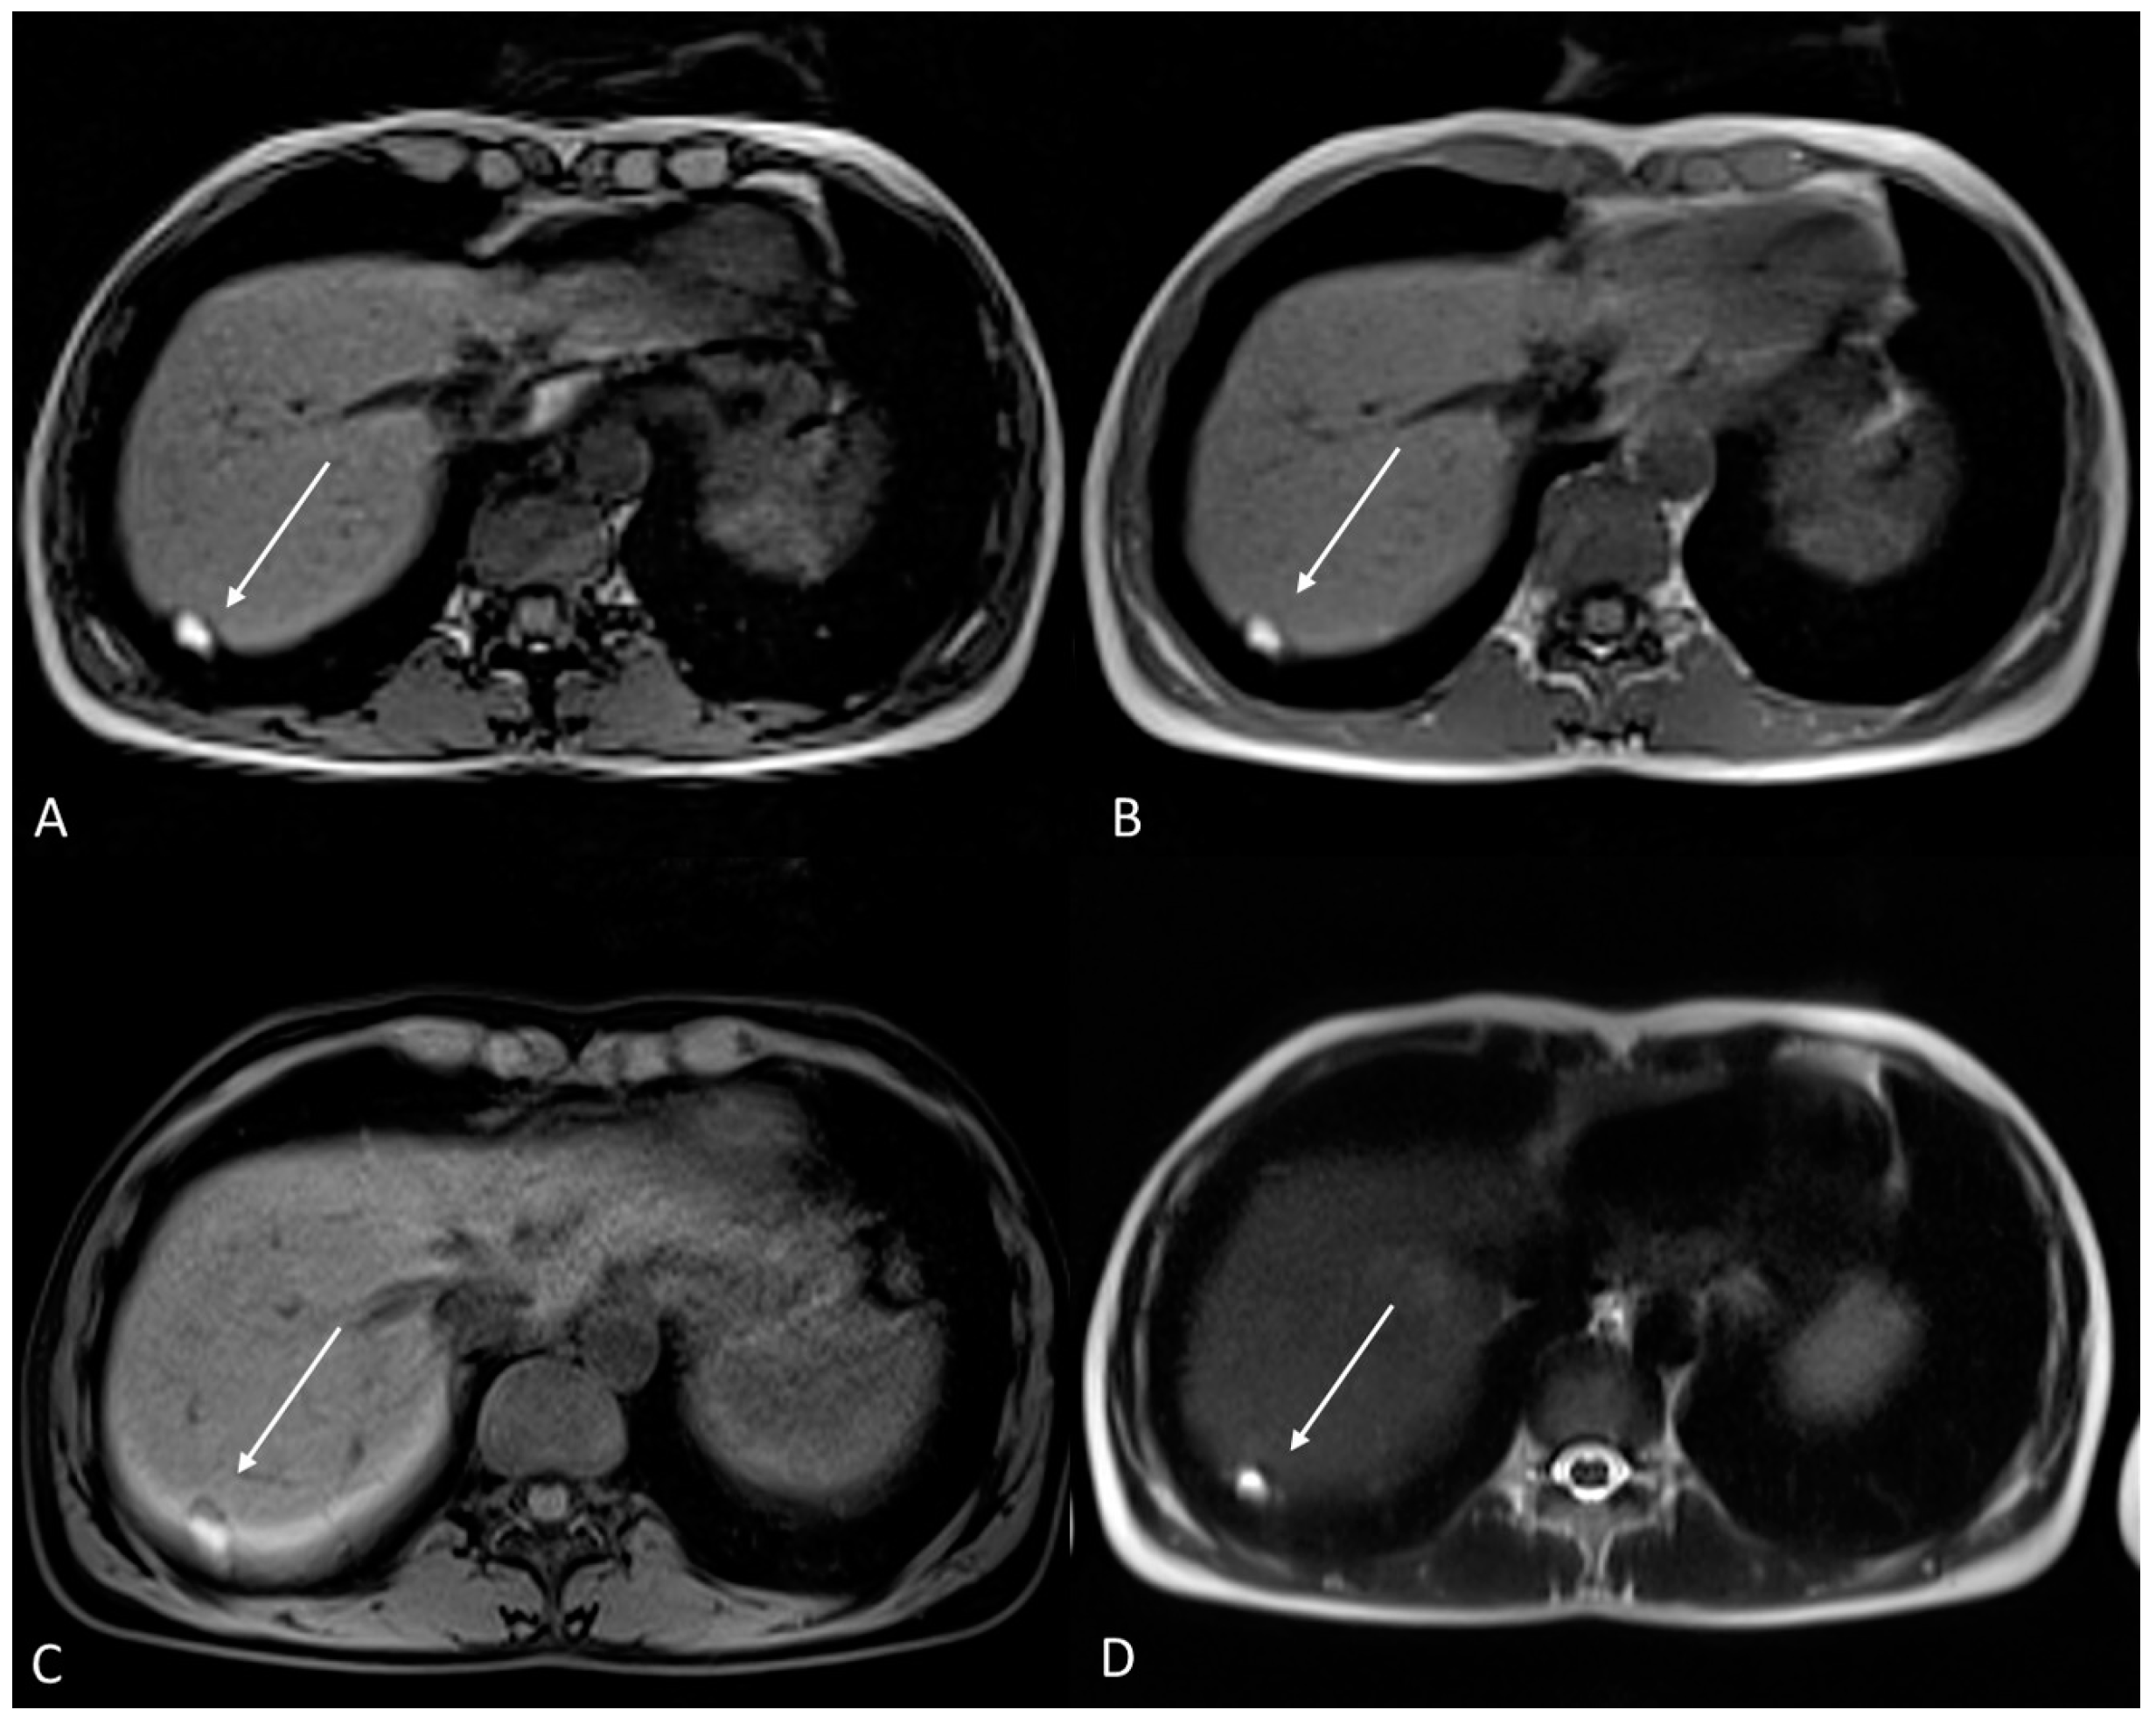

4. Ovarian Endometrioma